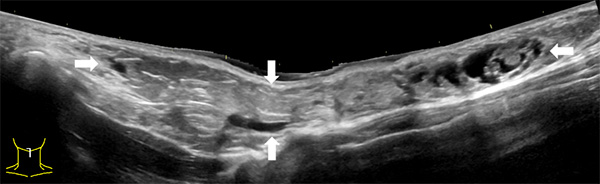

由于淋巴管畸形可发生在身体的任何部位,大多数发生在头颈部,其次为腋窝、纵膈及四肢。通常进行超声、磁共振、CT、诊断性抽液等检查,必要时依据情况进行穿刺活检,基本可以确诊。当怀疑患有淋巴管畸形时,应首先做超声检查,查清楚病变的部位、性质、大小及与周围组织的关系,评估是否需要治疗以及如何治疗。

淋巴管畸形超声:精准定位病灶部位范围以及与周边脏器的关系